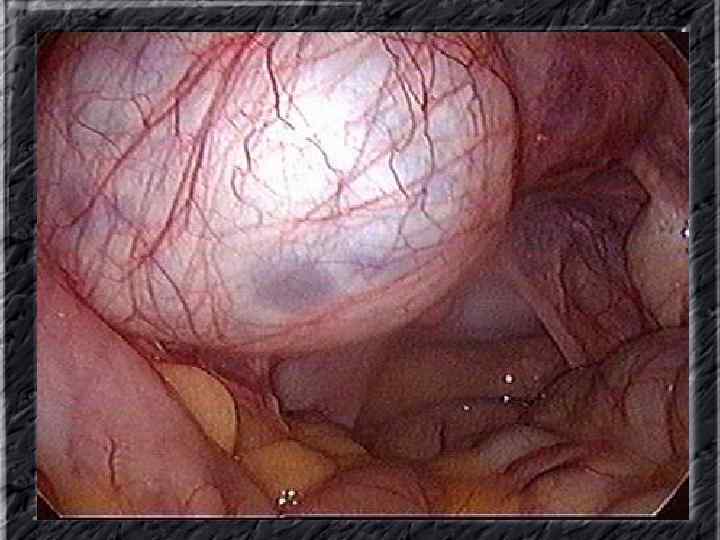

Названия слайдов: • • • Слайд 20. Ультрасонография: диффузная эхонеоднородность миометрия при внутреннем эндометриозе. Слайд 21. Эндометриоз матки: Пять маленьких очажков эндометриоза красно-коричневого цвета по задней поверхности матки; макропрепарат. Слайд 22. Множественная миома матки: видны субсерозные, субмукозные и интрамуральные узлы; макропрепарат. Слайд 23. Большая миома матки, подвергшаяся дегенеративным изменениям ( «красная дегенерация» ); макропрепарат. Слайд 24. Ультрасонография: интрамуральный узел фибромиомы, деформирующий контуры органа. Слайд 25. Ультрасонография: интрамуральный узел фибромиомы, деформирующий полость матки и смещающий эндометрий книзу. Слайд 26. Ультрасонография: субсерозный узел фибромиомы матки с эхопризнаками нарушения питания. Слайд 27. Лапароскопия: субсерозная фибромиома матки. Слайд 28. Лапароскопия: выраженный сосудистый рисунок на поверхности субсерозной фибромиомы матки. Слайд 29. Лапароскопия: выраженный сосудистый рисунок на поверхности субсерозной фибромиомы матки. Слайд 30. Большая цервикальная плоскоклеточная карцинома, которая простирается до влагалища; макропрепарат.